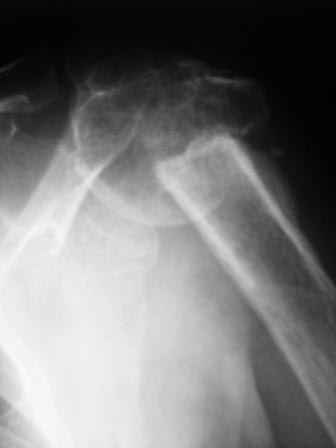

Уважаемые коллеги! Госпитализирована больная 51года. Травма - перелом хирургической шейки плеча в феврале 2009г.

Лечилась по месту жительства Лонгетной гипсовой повязкой. На фоне сформировавшегося ложного сустава работает маляром. Объем движений и сила естественно ограничены. При обсуждении тактики лечения возникли разногласия по поводу вида остеосинтеза и егоцелесообразности.